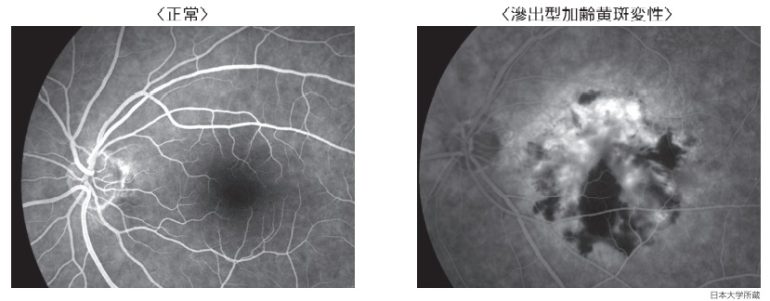

眼底検査

眼底に細い光を当て、網膜の状態を観察する検査です。

滲出型の場合は、出血や網膜のむくみなどが認められます。

正常な眼の眼底写真

滲出型加齢黄斑変性の眼底写真